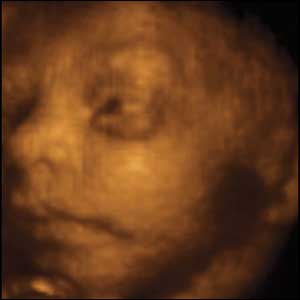

3- تكون هيئة الجنين قد اتضحت و يكون وجهه أكثرا بروزا.

انظري لفلذة كبدك فقد اصبح واضح المعالم